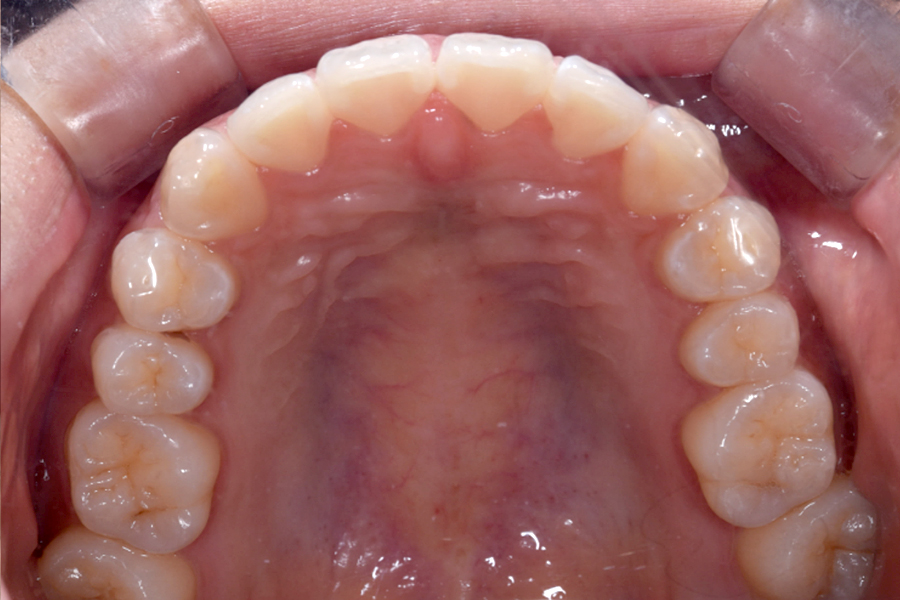

| 主訴 | 見た目を治したい、歯を白くしたい |

|---|---|

| 治療期間 | 1年6か月 |

| 治療費 | マウスピース矯正と ホームホワイトニングセット 1,022,350円(税込) |

| 治療内容 | 目立ちにくいマウスピース矯正 (非抜歯矯正) 歯と歯の間に隙間をつくることにより、歯列弓を広げながら治療を行いました。 また矯正用マウスピースをトレー代わりにし、ジェルを入れてホームホワイトニングを同時に行っております。 |

| 治療のリスク | ・後戻りする可能性があるのでリテーナーを最低でも矯正期間以上はつける必要があります。 ・ホワイトニング後、一時的に痛みが出る場合があります。 |